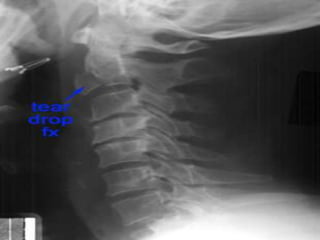

Flexion Teardrop Fracture C5-6

fracture is the result of a combination

of flexion and compression ,most commonly at C5-6

 The teardrop fragment comes from the

anteroinferior aspect of the vertebral body. The

larger posterior part of the vertebral body

is displaced backward into the spinal canal.



Best seen on lateral view

 It is an completely unstable fracture associated with

complete disruption of ligaments and anterior cord

syndrome and quadriplegia

 70% of patients have neurologic deficit.

common in MOTOR VECHICLE ACCIDENT

Signs:

Prevertebral swelling

associated with anterior

longitudinal ligament tear.

Teardrop fragment from

anterior vertebral body

avulsion fracture.

Posterior vertebral body

subluxation into the spinal

canal.

Spinal cord compression

from vertebral body

displacement.

Fracture of the spinous

process.